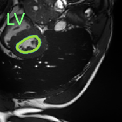

Despite their outstanding accuracy, semi-supervised segmentation methods based on deep neural networks can still yield predictions that are considered anatomically impossible by clinicians, for instance, containing holes or disconnected regions. To solve this problem, we present a Context-aware Virtual Adversarial Training (CaVAT) method for generating anatomically plausible segmentation. Unlike approaches focusing solely on accuracy, our method also considers complex topological constraints like connectivity which cannot be easily modeled in a differentiable loss function. We use adversarial training to generate examples violating the constraints, so the network can learn to avoid making such incorrect predictions on new examples, and employ the Reinforce algorithm to handle non-differentiable segmentation constraints. The proposed method offers a generic and efficient way to add any constraint on top of any segmentation network. Experiments on two clinically-relevant datasets show our method to produce segmentations that are both accurate and anatomically-plausible in terms of region connectivity.